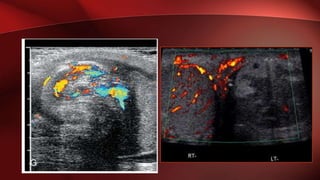

• Colour Doppler should reveal bilaterally symmetric and relatively

uniform flow through both testes and epididymides.

ULTRASOUND: COLOR DOPPLER

• Early Torsion

– No flow, echogenicity similar

• Late Torsion

– Heterogenous echotexture

– Increased extra testicular

blood flow

ULTRASOUND: COLOR DOPPLER •Early Torsion – No flow, echogenicity similar • Late Torsion – Heterogenous echotexture – Increased extra testicular blood flow